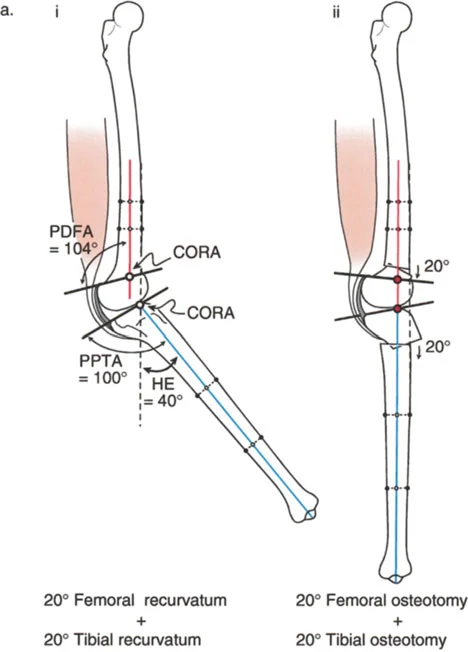

الارتداد الفخذي (Femoral Recurvatum):

- يحدث هذا عندما يكون هناك انحناء مفرط في الجزء السفلي من عظم الفخذ، مما يجعل الركبة تتمدد بشكل مفرط. يمكن أن ينجم عن توقف جزئي في النمو أو تشوهات خلقية.

- على سبيل المثال، قد يؤدي توقف النمو الجزئي في عظم الفخذ البعيد إلى تشوه ارتدادي فخذي بمقدار 20 درجة، مما يسبب فرط تمدد الركبة.

- مركز دوران الزاوية (CORA - Center of Rotation of Angulation): يتم تحديد هذا النقطة على الأشعة السينية لتحديد مكان التشوه العظمي بدقة، وهو أمر بالغ الأهمية لتخطيط عملية قطع العظم.

- الركبة الارتدادية بسبب تشوه مركب (فخذي وظنبوبي):

- إذا كان هناك ارتداد في كل من الفخذ والساق، وكان مجموع درجتي الارتداد يساوي درجة فرط التمدد الكلي للركبة.

- إذا كان هناك تشوه مركب مع تقلص انثناء مصاحب، فقد يكون فرط التمدد السريري أقل من مجموع التشوهات العظمية.

- إذا كان هناك ارتداد في كل من الفخذ والساق، وكان مجموع درجتي الارتداد يساوي درجة فرط التمدد الكلي للركبة.

2. العلاج الجراحي: قطع العظم (Osteotomy)

الهدف من جراحة قطع العظم هو إعادة محاذاة العظام وتصحيح التشوه الزاوي في المستوى السهمي، لاستعادة وظيفة الركبة الطبيعية واستقرارها.

أ. قطع العظم الفخذي لتصحيح الارتداد الفخذي:

- متى يتم إجراؤها: عندما يكون التشوه الرئيسي في عظم الفخذ البعيد.

- الإجراء: يتم إجراء قطع للعظم (عادة قطع عظم انثناء) في الجزء البعيد من عظم الفخذ، عند مركز دوران الزاوية (CORA)، لإعادة محاذاة العظم.

- الهدف: تصحيح فرط تمدد الركبة واستعادة المحاذاة الطبيعية.

- مثال: لتصحيح ارتداد فخذي بمقدار 20 درجة، يتم إجراء قطع عظم انثناء فخذي بمقدار 20 درجة.